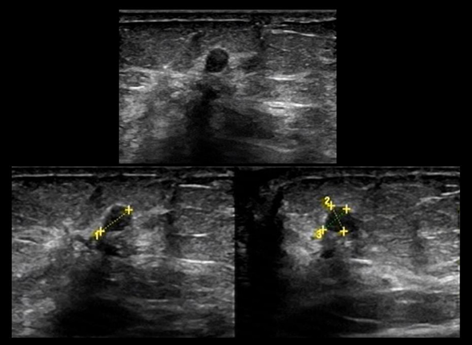

- HHUS: Chỉ ghi nhận một khối giảm âm - BI-RADS 3.

Hình 8. Khối giảm âm, giới hạn rõ trên HHUS

- ABUS: Ngoài khối u trên còn phát hiện thêm một khối giảm âm không đều, có gai nằm ngay phía sau - BI-RADS 4

Hình 9. Khối giảm âm, bờ rõ quan sát thấy trên ABUS (mũi tên vàng) và khối giảm âm, bờ không đều và có tua gai nằm ngay phía sau (mũi tên cam) – BI-RADS 4

Kết quả mô bệnh học: Sẹo hình tia (Radial scar)

Ý nghĩa lâm sàng: Với lát cắt và mặt phẳng quan sát đặc trưng (ví dụ coronal view) dày 2mm, ABUS cung cấp “bản đồ” cấu trúc mô vú rõ ràng hơn, giúp nhận diện các biến đổi kiến trúc mà siêu âm 2D đôi khi khó thể hiện trọn vẹn.